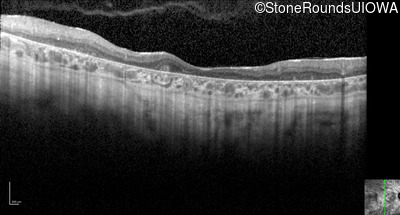

Optical Coherence Tomography - Left - 10/225

Exemplar / OCT Stack